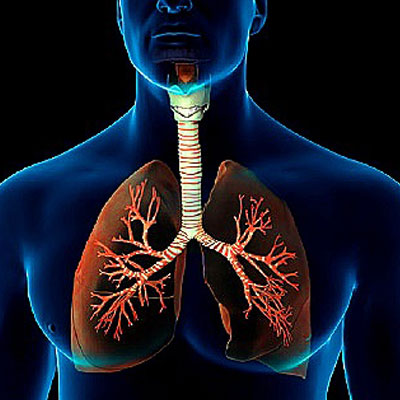

Diseases Treated

Spinal Problems Digestion Diseases Joints & Bones Problems Neurological Diseases Cardiovascular Disorders Respiratory Diseases Thyroid Problems Skin Diseases Diabetes Kidney Problems Male Reproductive Diseases Gyanecological Problems Opthalmic (Eyes) Problems Auto Immune Diseases Children Problems Hair Problems Addiction Rehabilation of Accidential Cases